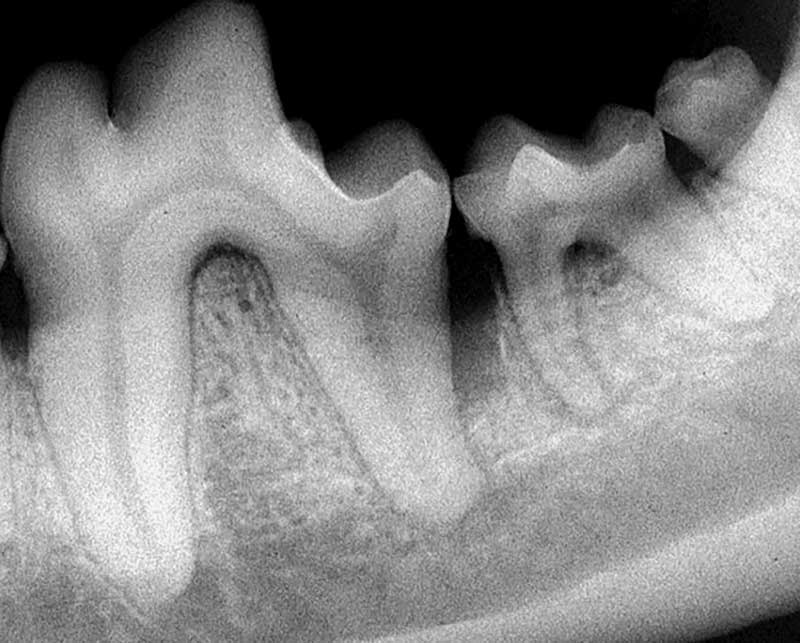

Figure 1: Generalized horizontal bone loss of teeth 405, 406, and 407. Teeth 405 and 406 will likely require extraction due to the severity of bone loss, root exposure, and furcation involvement. Photos courtesy John Lewis

Periodontal bone loss can be lumped into two categories: horizontal and vertical bone loss. Horizontal bone loss is a term describing alveolar bone loss occurring along the alveolar margin of the mandible or maxilla, resulting in root exposure and furcation exposure of multi-rooted teeth (Figure 1). Vertical bone loss is alveolar bone loss occurring along the long axis of a root (Figure 2).